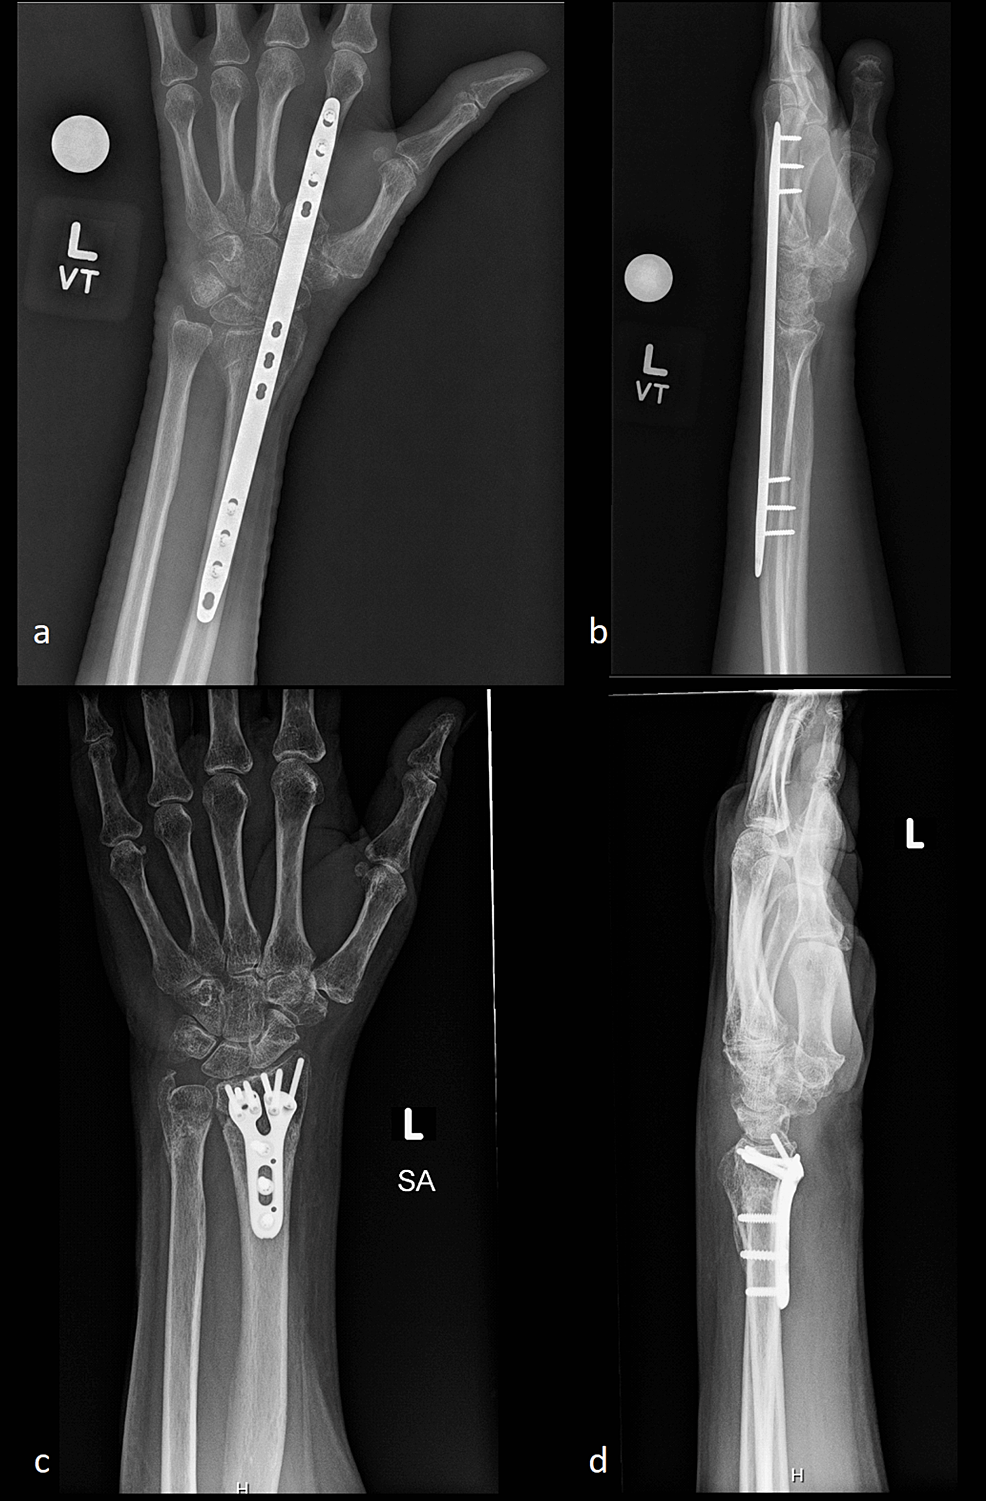

Roh Procedure . Roh in orthopaedic commonly refers to removal of hardware, a surgical procedure to take out implanted devices or materials from the body. Recent evidence has suggested that a laparoscopic rather than an open approach to reversal of hartmann's procedure (roh) may be. Many distal radius fractures are treated with a volar locking plate, but a minority undergo dorsal bridge plate fixation. Aims restoration of bowel continuity after hartmann's procedure (roh) can be challenging and associated with considerable morbidity. Roh in medical commonly refers to removal of hardware, a surgical procedure to extract implants or devices previously inserted in the body. In recent years single incision laparoscopic surgery (sil) has tried as feasible minimally invasive operation.